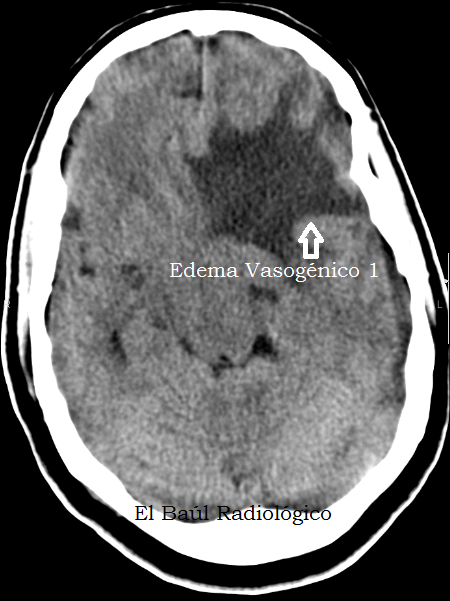

El más importante de todos es el edema vasogénico, porque es un signo indirecto de la existencia de un proceso patológico intracraneal, que podría pasar desapercibido en una exploración de TC o TRM. En este tipo de edema se produce un aumento de la permeabilidad de los capilares normales del cerebro porque están comprimidos por una lesión ocupante de espacio intracraneal o porque hay un fenómeno de angiogénesis tumoral que produce arteriolas patológicas. El edema vasogénico cerebral puede estar producido por un tumor maligno, uno benigno, una infección o un traumatismo. El líquido extravasado difunde por la sustancia blanca cerebral contorneando la corteza, motivo por el que se presenta como un área hipodensa de contorno digitiforme. Suele producir efecto de masa importante. ¿Pero, cual es la causa que produce el edema vasogénico? La utilización de contraste suele solucionar esta duda.

(Vasogenic edema, is an indirect sign of the existence of an intracranial pathologic process that could go undetected in a CT or MRI scans. In this type of edema there is an increase of permeability of normal brain capillaries that are compressed by a intracranial space occupying lesion or because there is a phenomenon of tumoral angiogenesis. The cerebral vasogenic edema can be caused by a malignant tumor, a benign, infection or trauma. The extravasation of liquid diffuses throught cerebral white matter, outlining the cortex, why is presented as a hypodense digitiform area. It usually causes significant mass effect. But, what is the cause that produces vasogenic edema? The use of iodinated endovenous contrast usually solve this doubt)

FIGURA 1) En esta imagen se aprecia edema vasogénico en la sustancia blanca del lóbulo frontal izquierdo. No podemos identificar la causa.

(This image shows a large area of vasogenic edema in the white matter of the left frontal lobe).